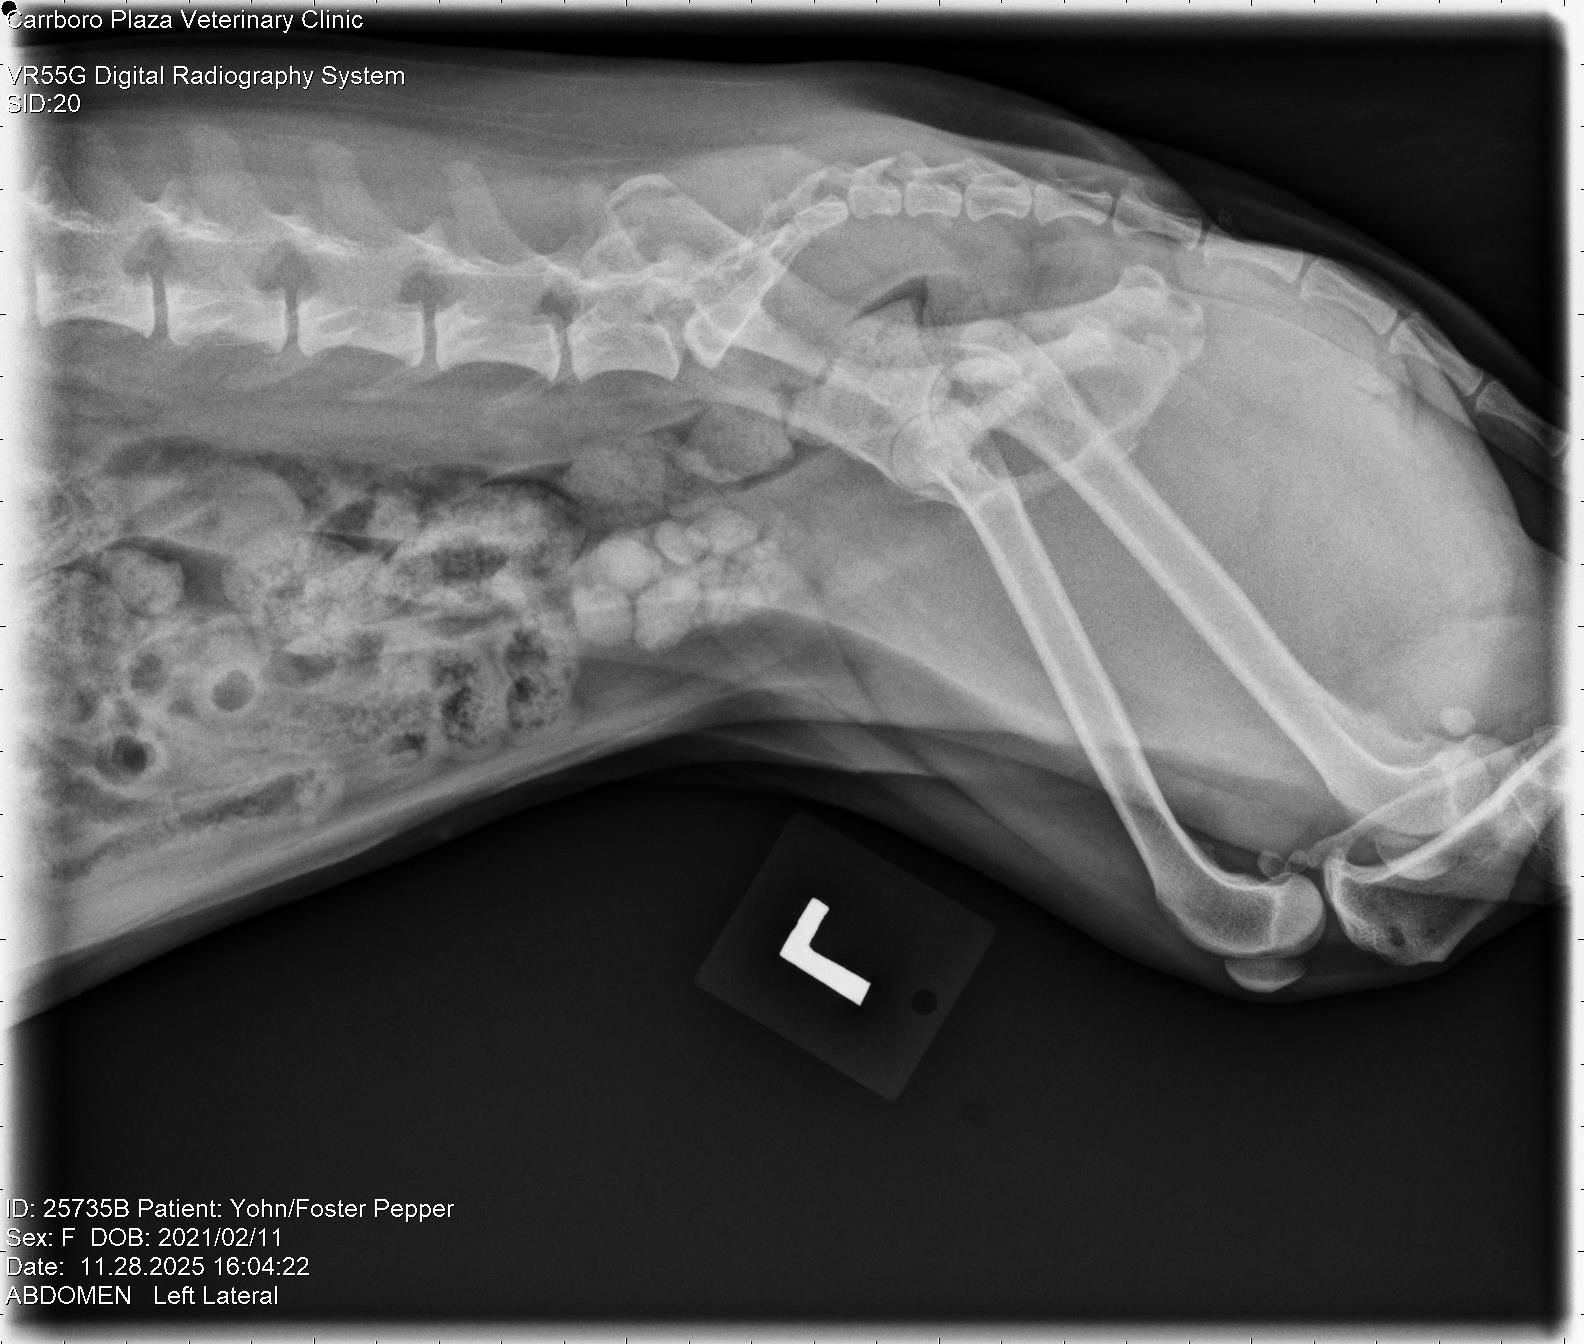

Family and friends, Pepper, our 4 year old, beautiful and perfect little girl is having a hard time. We found out very recently, after several vet visits that she has bladder stones. Several, in fact, and will require emergency surgery next week.